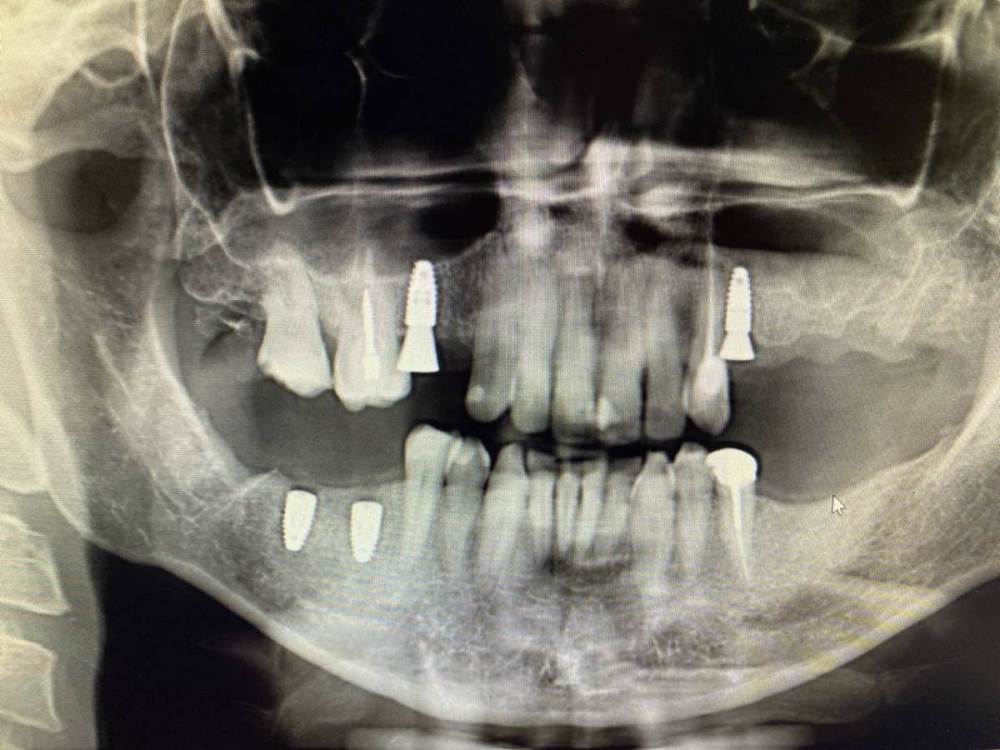

It'sGeorgy Опубликовано 3 февраля, 2022 Поделиться Опубликовано 3 февраля, 2022 (изменено) Коллеги, подскажите, с чем может быть связано такое настолько серьезное искажение на ОПТГ? 2 месяца думал, что завалил 1.5 в другую сторону, а на новом КТ оказалось все правильно. Скрытый текст Изменено 3 февраля, 2022 пользователем It'sGeorgy Ссылка на комментарий

kamranchick Опубликовано 3 февраля, 2022 Поделиться Опубликовано 3 февраля, 2022 лучше всего прицельник с позиционером, что оптг что кт не дают точной картинки, тем более штрауманн фонит будь здоров Ссылка на комментарий

It'sGeorgy Опубликовано 3 февраля, 2022 Поделиться Опубликовано 3 февраля, 2022 @kamranchick да, согласен, что лучше локсима + прицела после установки нет ничего. Но когда винтов много - просадка по времени получается, плюс асси с прицелом не всегда дружат. Но вышеуказанная ОПТГ дала повод задуматься целесообразности её в целом, если там настолько искажать может. 27 минут назад, kamranchick сказал: тем более штрауманн фонит будь здоров А разные винты с разной интенсивностью фонят? Не знал. Ссылка на комментарий